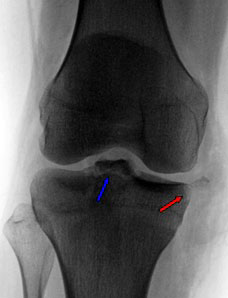

Röntgenfoto

Op een gewone röntgenfoto van de knie worden meestal geen afwijkingen gezien. Soms is er sprake van een fractuur nabij de aanhechtingsplaats van de voorste kruisband (avulsie fractuur), soms wordt een fractuur gezien aan de voorbuiten zijde van het scheenbeen net onder de gewrichtsspleet (Segond fractuur). Indien deze laatste fractuur wordt geconstateerd, is de diagnose vrijwel zeker.